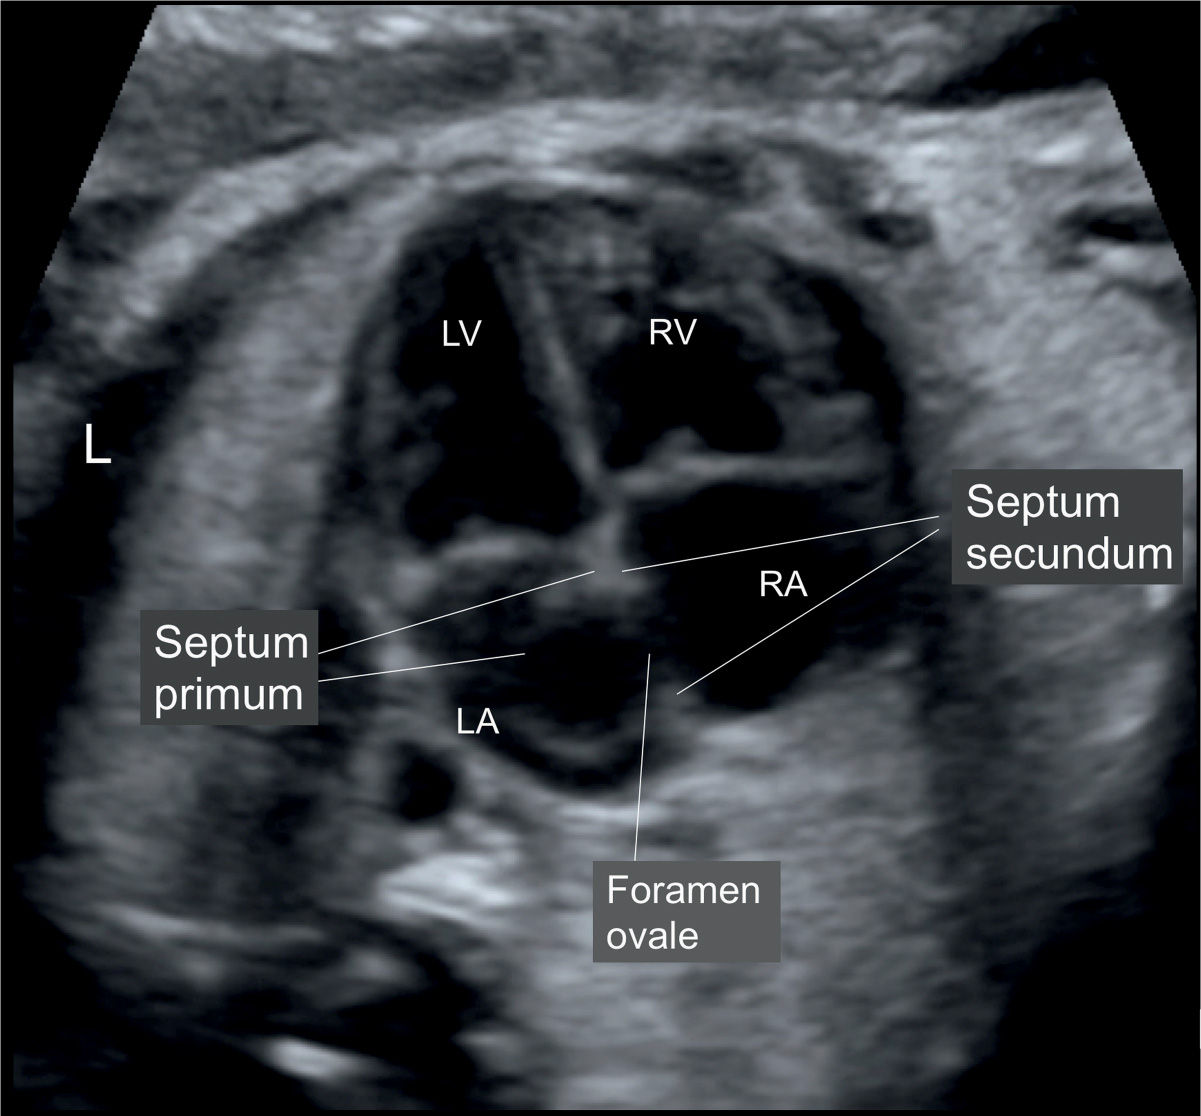

Cardiac Chambers The FourChamber and ShortAxis Views Obgyn Key Coronary Band Heart This is a crucial function for myocardial function and. In addition to these muscular ridges, a band of cardiac muscle, also covered by endocardium, known as the moderator band (see figure 19.1.8) reinforces the thin walls of the right ventricle and plays a. The coronary arteries run along the coronary sulcus of the myocardium of the heart. Their main function. Coronary Band Heart.